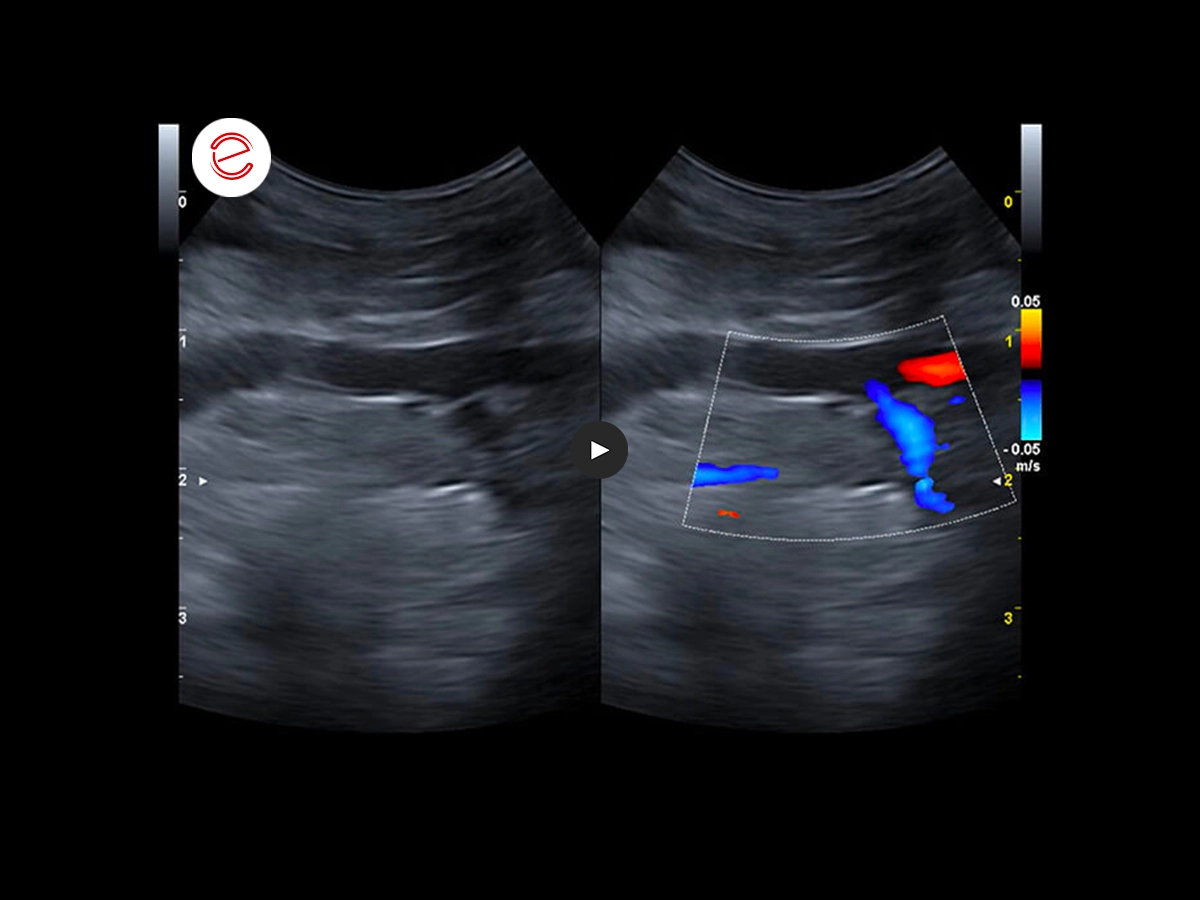

Ecografia del fegato

L'esame ecografico del fegato ha evidenziato un pattern ecogeno aumentato e non omogeneo.

Con l'ecografia epatica sono stati valutati anche i flussi della vena porta e il flusso splenico è risultato invertito (codice colore blu).

Si sospettava uno shunt porto-sistemico e per confermarlo è stato eseguito un test di gorgogliamento inoculando nella milza una miscela agitata di sangue e soluzione fisiologica. Contemporaneamente è stata eseguita una valutazione cardiaca iniziale.

La valutazione, in concomitanza con il test di gorgogliamento, ha evidenziato piccole bolle iperecogene nell'atrio destro.